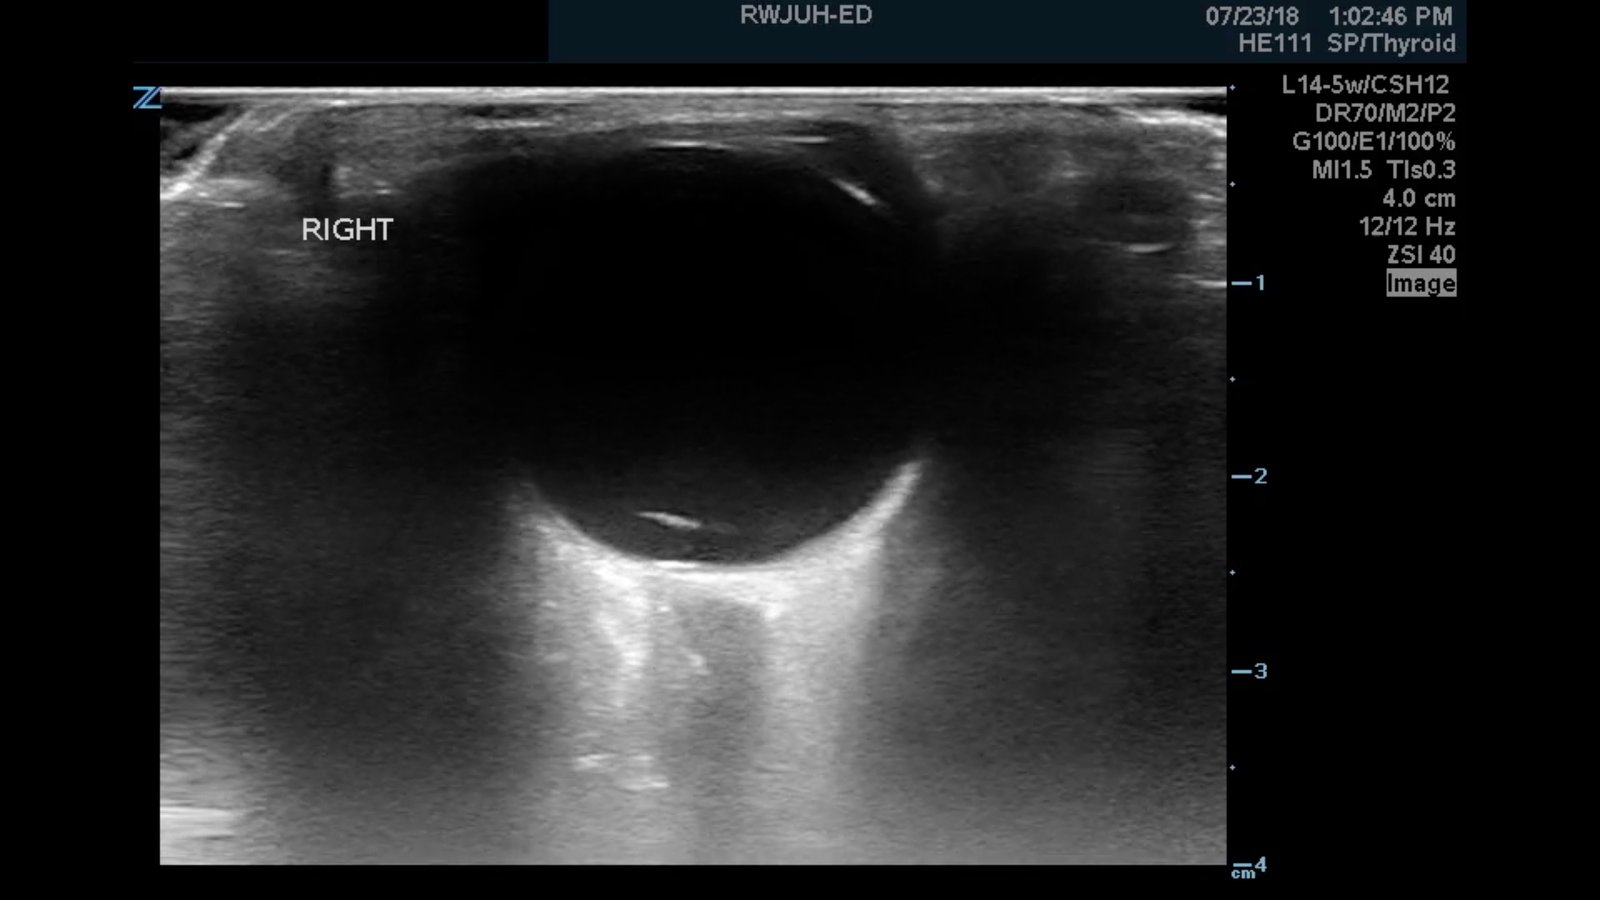

Ocular ultrasound was performed and demonstrated a thin, slightly echogenic strand (blue arrow) extending from the posterior eye into the vitreous humor (yellow arrow) which was hyperkinetic with extraocular motion. These findings are consistent with a posterior vitreous detachment (PVD).

Retinal detachment presents in ocular ultrasound as a taut, hyperechoic strand that moves in conjunction with extraocular movement. Posterior vitreous detachment presents as a much thinner and less echogenic strand that is hyperkinetic and wave-like with extraocular movement, described as swaying seaweed in appearance.6,7,8,9